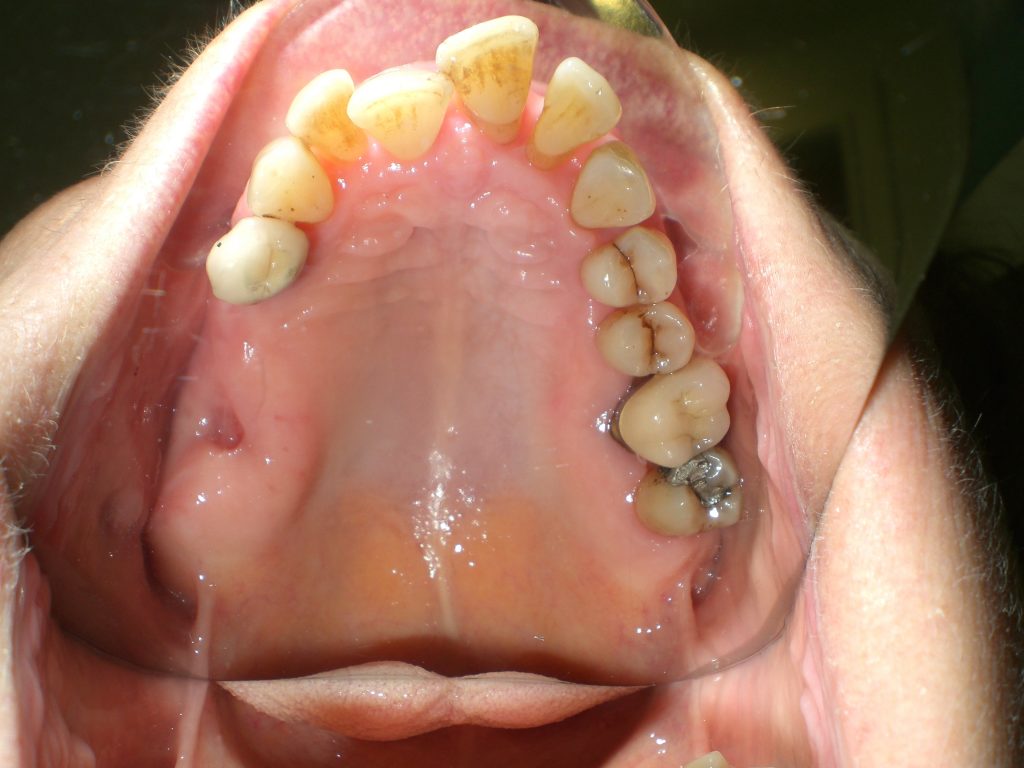

Arcade mandibulaire avant traitement orthodontique, séquelles de maladie parodontale

Après traitement orthodontique et réalisation d’une attelle fibrée (courtoisie Dr Patrick Fournier)

Arcade maxillaire avant traitement orthodontique, séquelles de maladie parodontale

Après traitement orthodontique et réalisation d’une attelle coulée collée (courtoisie Dr Patrick Fournier)